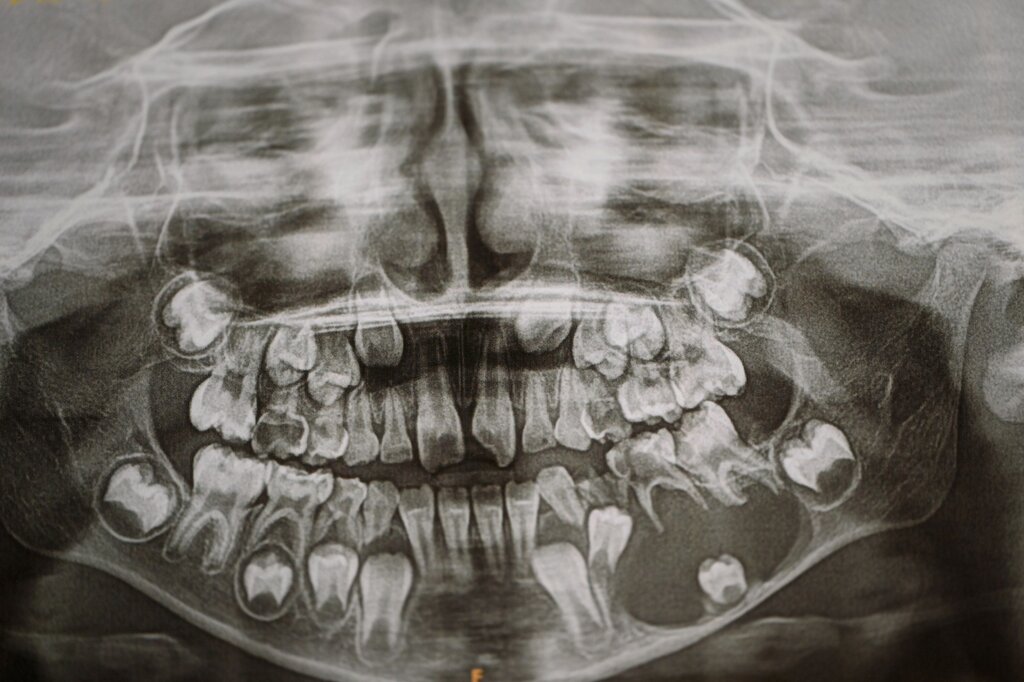

Hinzu kommen erhebliche Defizite in der Fort- und Weiterbildung: Eine fachzahnärztliche Spezialisierung findet praktisch nicht statt, was sich im fachlichen Austausch mit den lokalen Kolleginnen und Kollegen widerspiegelt. Die Zahnmedizin befindet sich vielfach noch in einer kurativen Phase, während westliche Gesundheitssysteme längst präventiv ausgerichtet sind. Diese strukturellen Defizite zeigen sich unmittelbar im klinischen Alltag. Der Stellenwert der Zahngesundheit ist – auch bedingt durch die langjährige Krisensituation – deutlich geringer als in westlichen Ländern. In Kombination mit einer zuckerreichen Ernährung weisen bereits Kinder häufig ausgeprägte kariöse Läsionen auf. Die unbehandelten Entzündungen und der oft frühzeitige Zahnverlust führen zu funktionellen Einschränkungen und erschweren spätere chirurgische Eingriffe erheblich.

Der Behandlungsschwerpunkt des Einsatzes lag auf der operativen Versorgung von Kindern mit Lippen-Kiefer-Gaumenspalten, großen zystischen Läsionen sowie dysgnathiechirurgischen Fragestellungen. Gerade bei den LKG-Patientinnen und -Patienten zeigte sich die enge Verzahnung zwischen Zahnmedizin, Kieferorthopädie und Chirurgie – und gleichzeitig die strukturellen Limitationen der Behandlung in Palästina. Häufig stellten sich die Kinder mit ausgeprägter Karies, entzündlichen Veränderungen und einer fehlenden kieferorthopädischen Vorbereitung vor. Zudem fehlt eine strukturierte interdisziplinäre Zusammenarbeit, etwa mit der HNO-Heilkunde und der Logopädie.